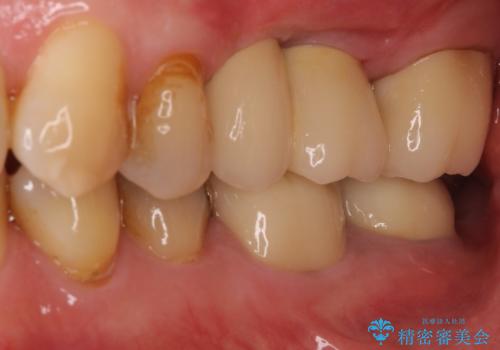

部分矯正を併用した奥歯のインプラント補綴治療

部分矯正期間中はアンカースクリューやフック、ゴムなどが粘膜にあたり、大変な思いをすることになりましたが、そのおかげでインプラント補綴した歯と最後方歯の位置が非常に良好となり、まるでご自身の歯のように咬むことができるようになりました。